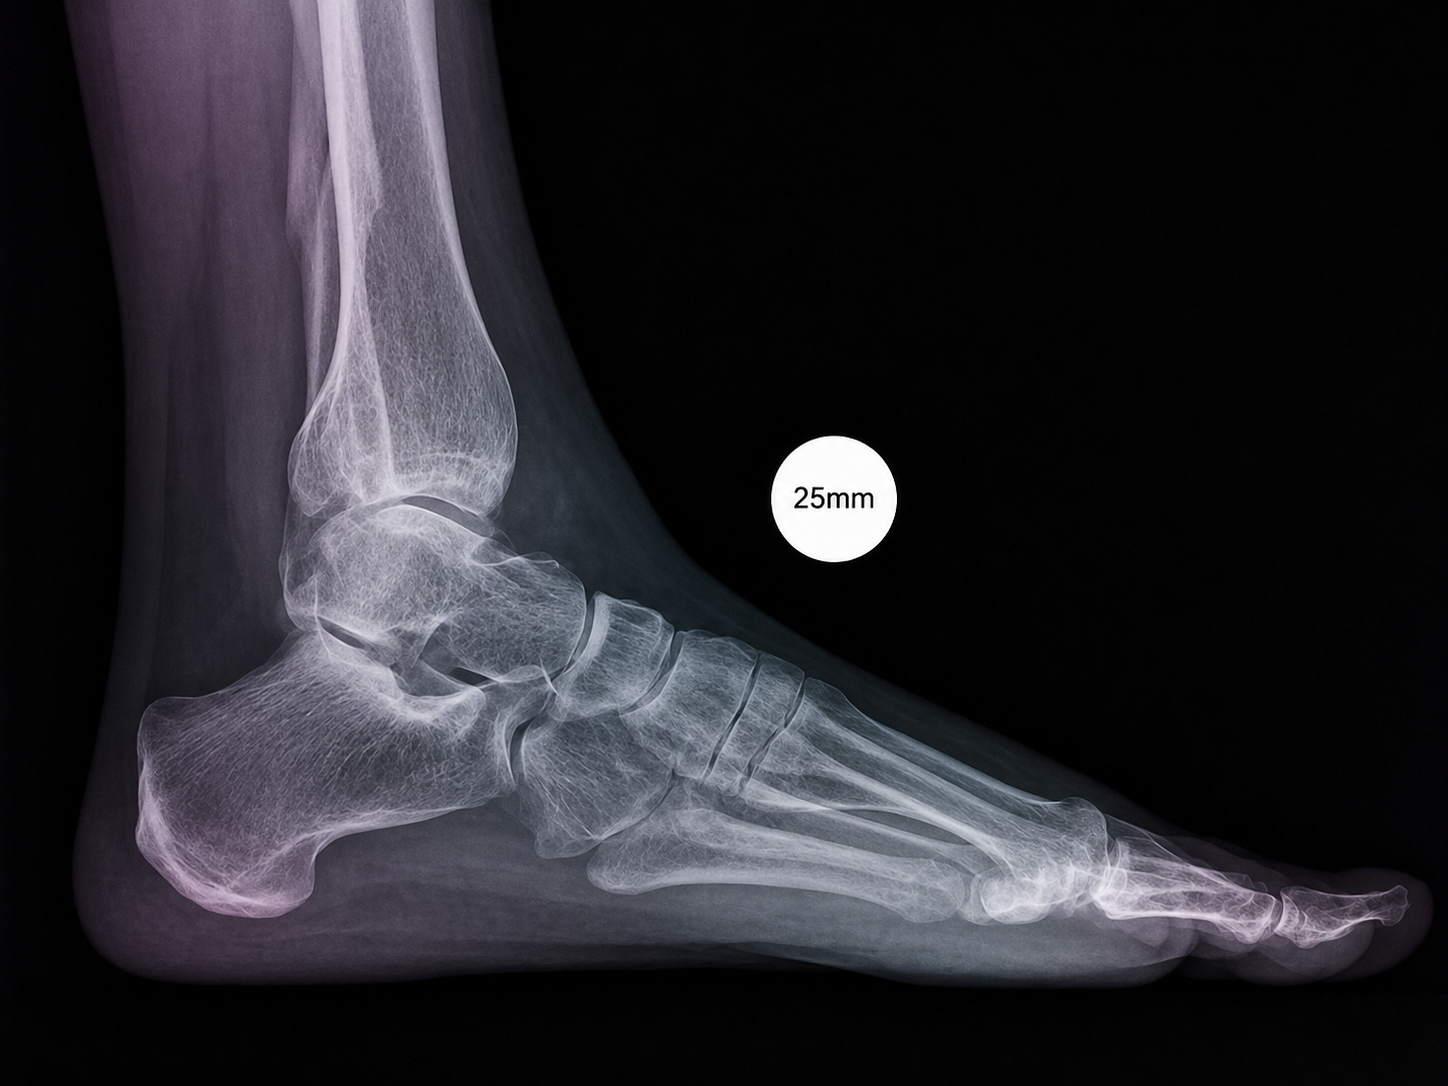

A compact guide for radiology teams on correct calibration sphere placement in orthopedic X-ray imaging. The marker must be positioned in the anatomical plane of the target joint so that digital scaling, measurements and preoperative templating remain clinically reliable.